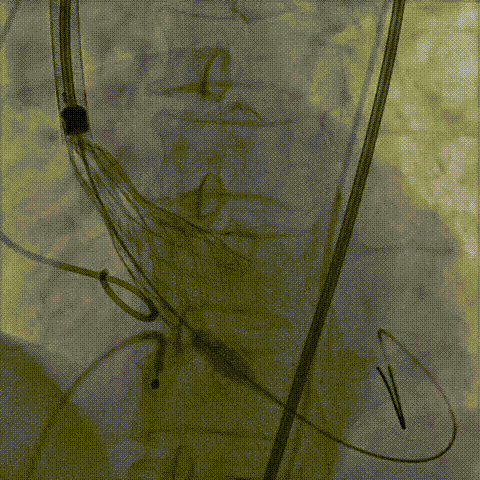

手术影像:

输送器柔顺过弓、跨瓣

瓣膜开始定位

瓣膜逐步释放到工作位

瓣膜工作位造影,位置良好

瓣膜完全释放